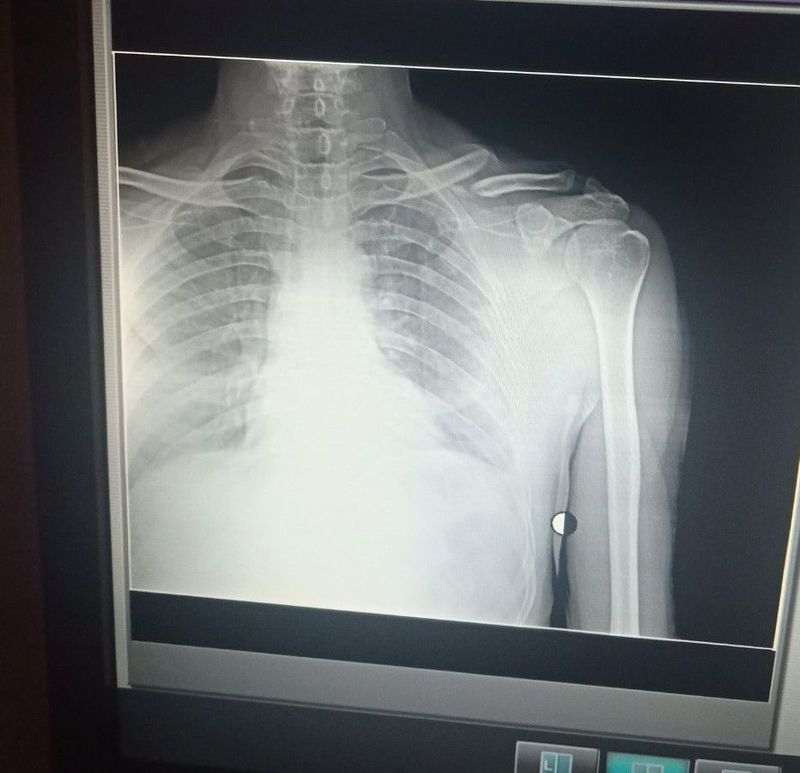

Left side clavicular bone

Bone

Orthopedicsurgery

Extremity